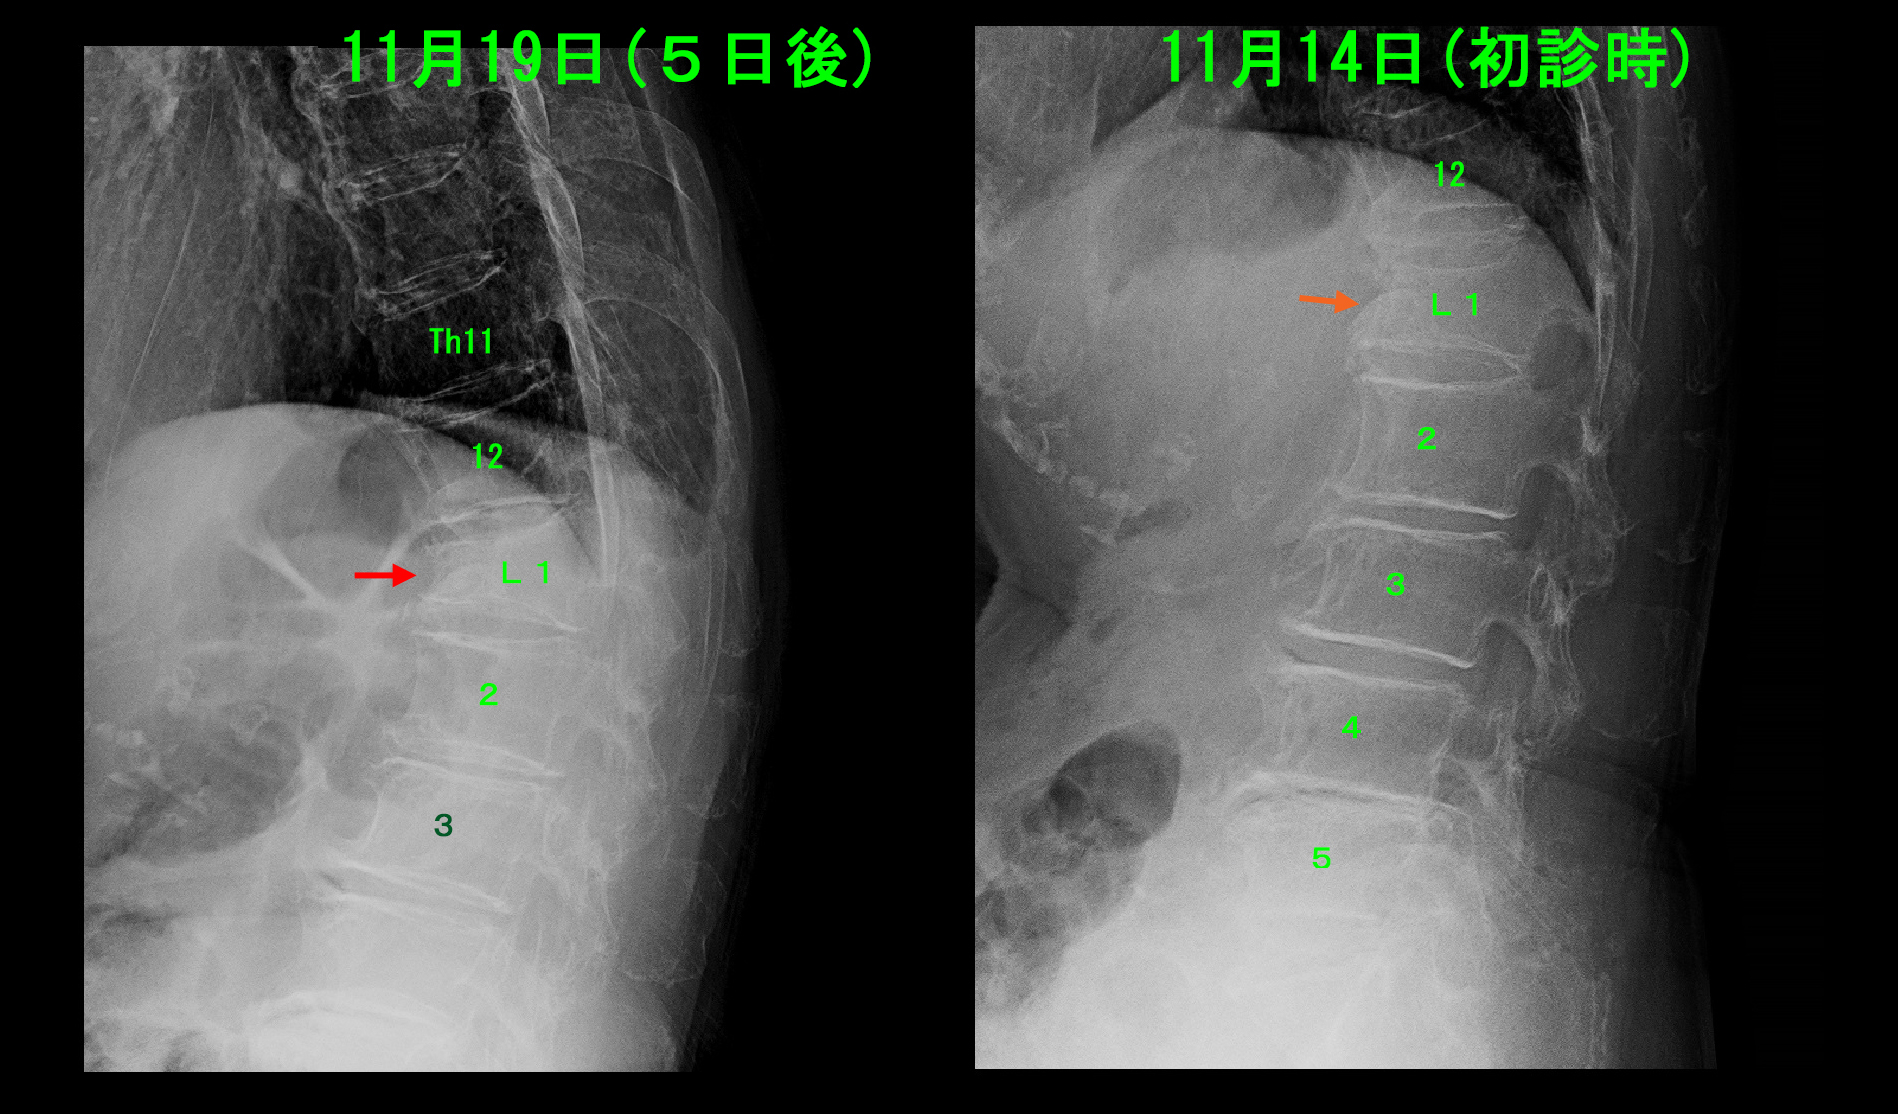

81才の女性で、当院近隣にお住まいの方です。令和6年11月14日に当院を受診されました。11月3日より腰痛が悪化し、11月9日に比較的遠方の外科を受診して投薬を受けています。外科の専門は消化器で運動器の専門家ではありません。近隣の専門家の当院を回避して専門でない外科を受診する姿勢が私には理解できませんが、私がそう思っても仕方のないことです。外科の投薬は効果を出さずに、11月12日には寝返りができなくなり、不眠となりVAS10の痛みとなったようです。

81才女Xp1.jpg

レントゲン像では第1腰椎(L1)が他の背骨(椎体といいます)に比して扁平化しており(赤矢印)、圧迫骨折が疑われます。当院では高齢者の腰痛ではレントゲン像では診断できない圧迫骨折がしばしばあるため、必ずMRI検査を勧めています。

11月19日(初診5日後)夜中に腰痛が悪化して体動困難となったと、また受診してきました。私の指示を守っていないので、圧迫骨折が悪化したことが容易に想像されます。レントゲン像では5日間で14mmL1椎体の扁平化が進行しました(オレンジ矢印→赤矢印)。圧迫骨折ではある程度の椎体の扁平化の進行は仕方ありませんが、安静が保たれていないため急速に壊れが進行しました。電動ベッドが導入されたのは初診後3週経過してからですが、圧迫骨折を悪化させないためにはできるだけ早期に電動ベッドを導入することが重要なのです。初期の3週間の間に圧迫骨折の扁平化は進行してしまいます。この方は他疾患もあり元々担当のケアマネージャーさんがいたのですが、ケアマネジャーさんによれば、初診から10日ぐらいは2階にも上がり下りしていたとのことでした。